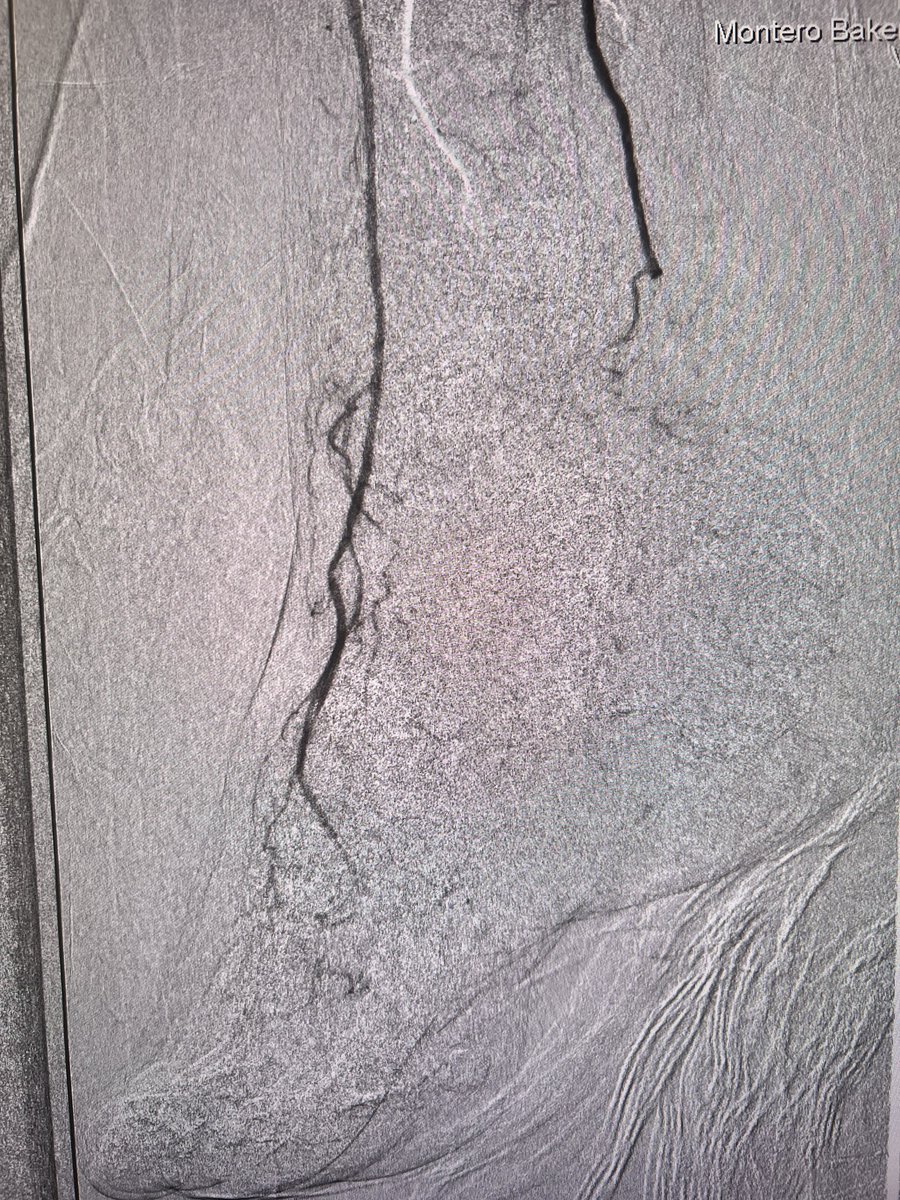

Curious if #CLIFighters feel there is a relationship between revasc of lower extremities and amputation in any center?